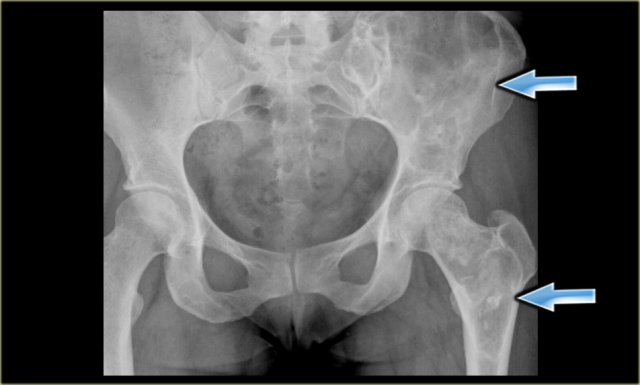

On the left a patient with a chondrosarcoma of the right acetabulum.

On the CT expansion and subtle calcifications are present.

On the coronal T2-weighted image the tumor is seen as a large lobulated mass with very high SI, which is typical for chondroid tumors.

The T1-weighted image after Gd shows typical peripheral nodular enhancement.

In the center there is no enhancement.

This is probably due to a large myxoid component. .